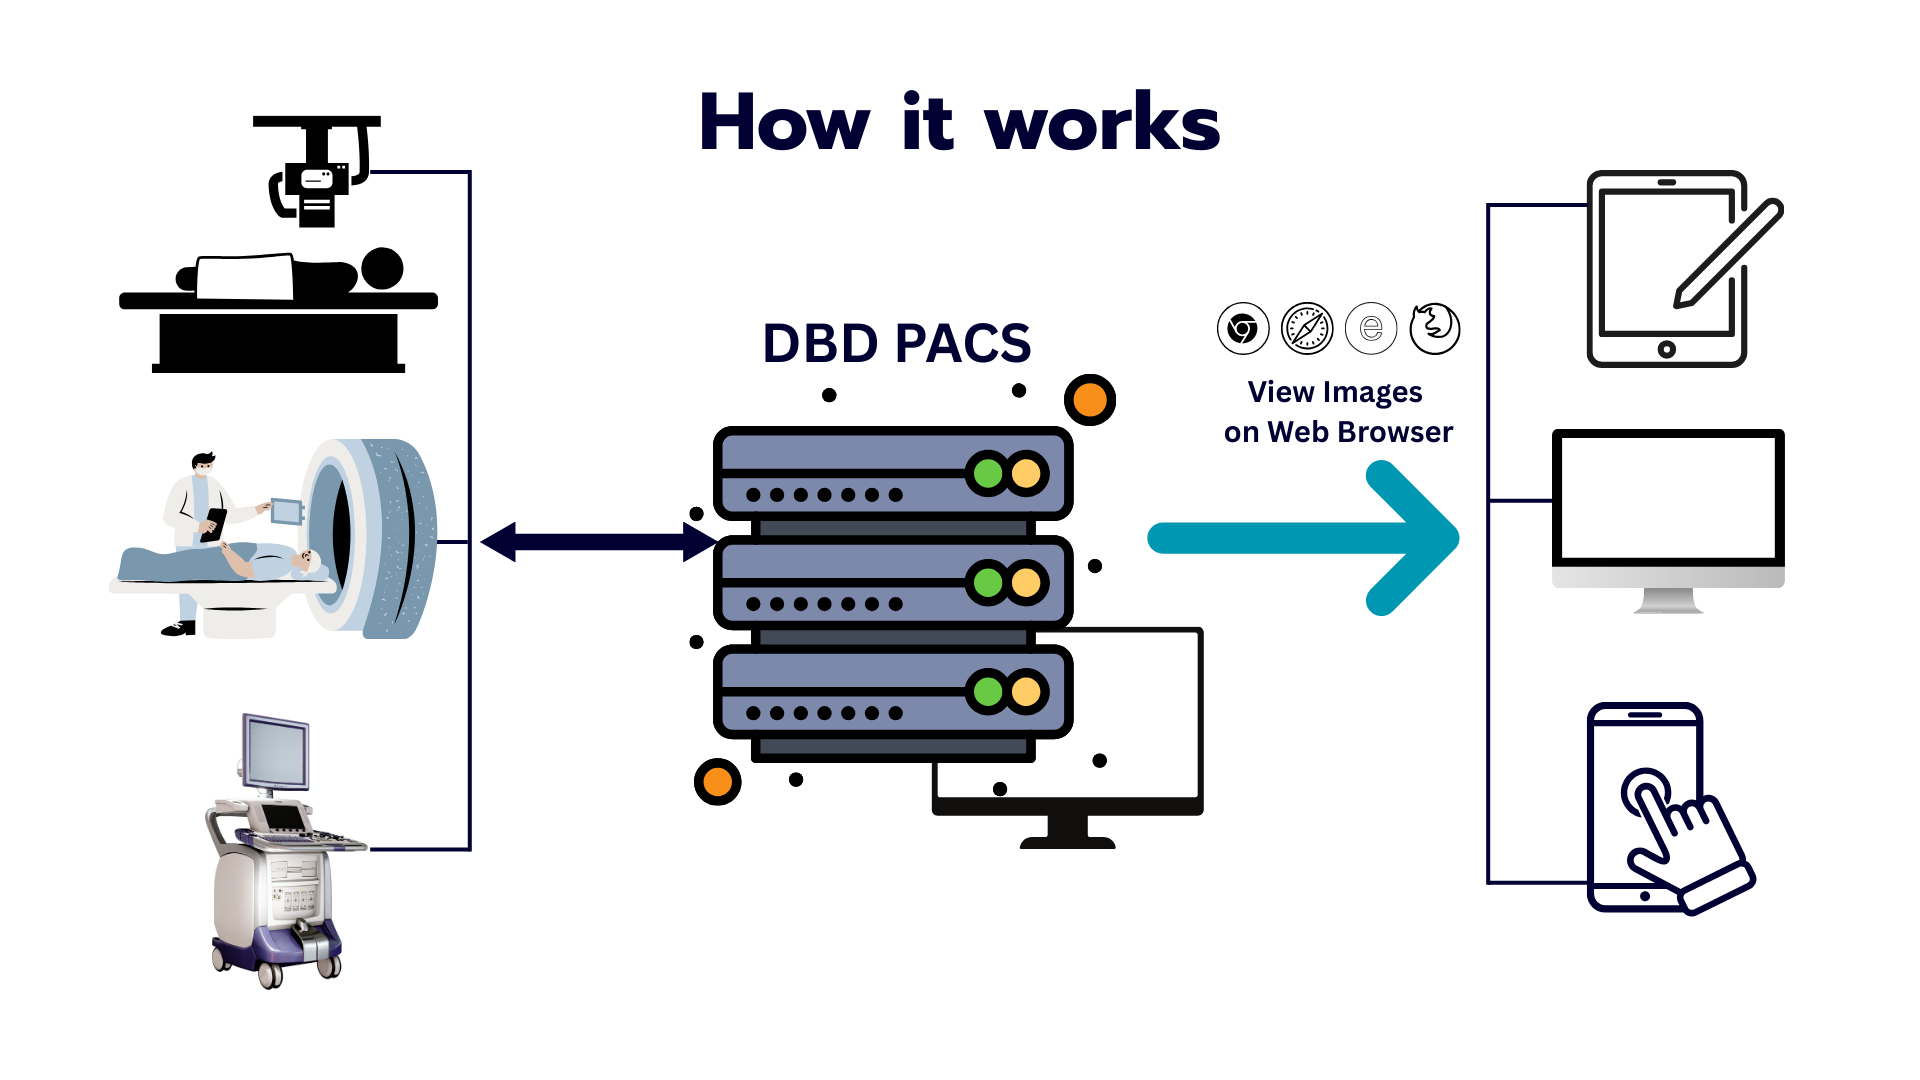

เครื่องมือแพทย์ส่งภาพเข้า DBD PACS โดยตรง แพทย์และรังสีแพทย์เรียกดูได้ทันทีผ่านทุกอุปกรณ์

X-Ray, CT, MRI, Ultrasound และอื่นๆ ถ่ายภาพผู้ป่วยในรูปแบบ DICOM

ระบบรับภาพอัตโนมัติ จัดเก็บปลอดภัย เข้ารหัส AES-256 พร้อม Backup ทุกวัน

ดูภาพ DICOM คุณภาพสูงได้ทันทีบน PC, Tablet หรือมือถือ ไม่ต้องติดตั้งโปรแกรม